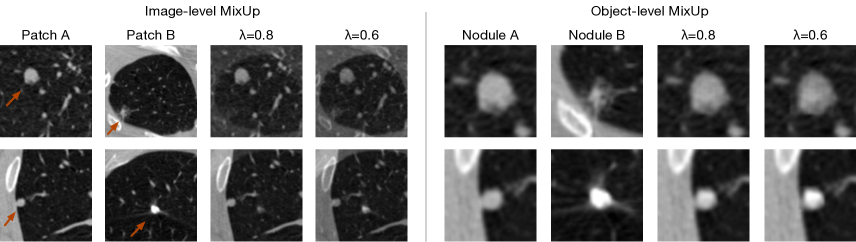

MixUp Augmentation. In FocalMix, two MixUp strategies are designed for medical images: image-level MixUp and object-level MixUp. As shown in table 3, the image-level MixUp can boost the CPM score from 0.852 to 0.867, and the object-level MixUp further improves the result to 0.872. We also illustrate some examples of MixUp in Figure 4. Intuitively, the goal of image-level MixUp is to encourage models to perform linearly between foreground and background, while object-level MixUp encourages models to detect lesions with richer patterns.

Refer to caption

Figure 4: Illustrative examples for two MixUp methods. The left figure shows the image-level MixUp, where red arrows point to nodules in the original image. The right figure demonstrates the object-level MixUp, where we zoom in on the nodules and locate them in the center of each image patch for better visualization.